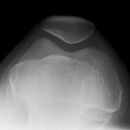

Patella Defilée

Patient sitzt auf dem Tisch, Knie angewinkelt, Ferse unterpolstert, so dass die Patella parallel zum Tisch verläuft bzw. die Strecke Ober- und Unterschenkel zum gleichschenkligen Dreieck wird.

1. Aufnahme:

Winkeleinstellung des Knies von 60° mit Hilfe selbst angefertigter Winkelmesser z.b. aus Karton, tangierender Verlauf entsprechend von Oberschenkelknochen (Femur) und Unterschenkelknochen (Tibia), die Spitze liegt unterhalb der Patella. Kassette auf Femur senkrecht, bei der 60° Aufnahme sind der Oberrand und Unterrand der Patella deckungsgleich, sie entspricht der Patellaspezialaufnahme.

2. Aufnahme:

Grundlagerung bleibt bestehen, Winkel des Knies 30°, hier ist der FOA größer, es wird der obere (proximale) Rand der Patella abgebildet (Vergrößerung).

3. Aufnahme:

Grundlagerung bleibt bestehen, Winkel des Knies 90°, kleiner FOA, dargestellt wird der untere (distale) Patellarand.

Zentralstrahl

Röhre um 90° gekippt, zielt auf den Unterrand der Patella.

Dysplasie (Stufenbildung), Fraktur, Arthrose.

Freier Durchblick durch das Femoropatellargelenk und überlagerungsfreie Darstellung der Patella.